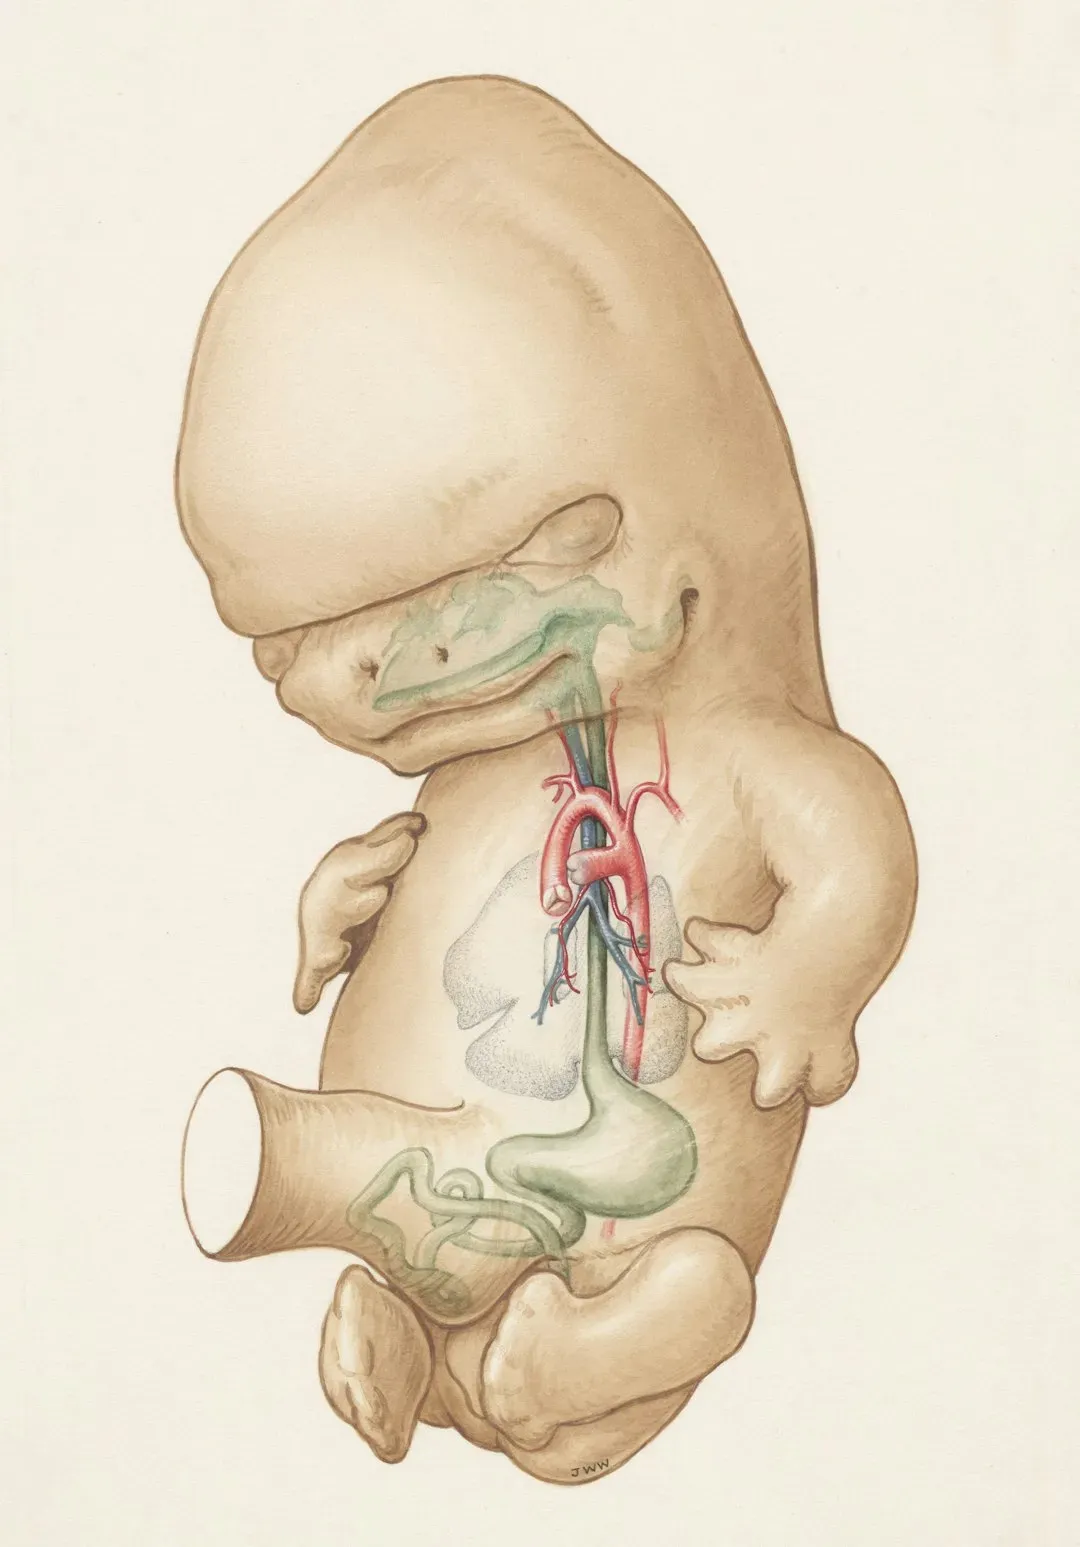

Perhaps nowhere is the puzzle more urgent than figuring out when consciousness first emerges in a developing human. Its neural correlate emerges around 24 weeks of gestation in the human foetus, when the nerves from the sensory organs are connected to the cortex via the thalamus. This timing has massive implications for medical ethics, premature infant care, and our understanding of fetal experience.

Using fetal magnetoencephalography (MEG), Moser and her team discovered that a version of this response could be found not only in newborns but also in 35-week-old fetuses. The evidence points toward some form of awareness emerging in late pregnancy, though what that experience actually feels like remains unknowable. A newborn infant is aroused and wakes up at birth, due to the enormous sensory stimulation and stress that it undergoes during the transition from an aquatic environment to air. Birth itself might represent a dramatic threshold in conscious experience.